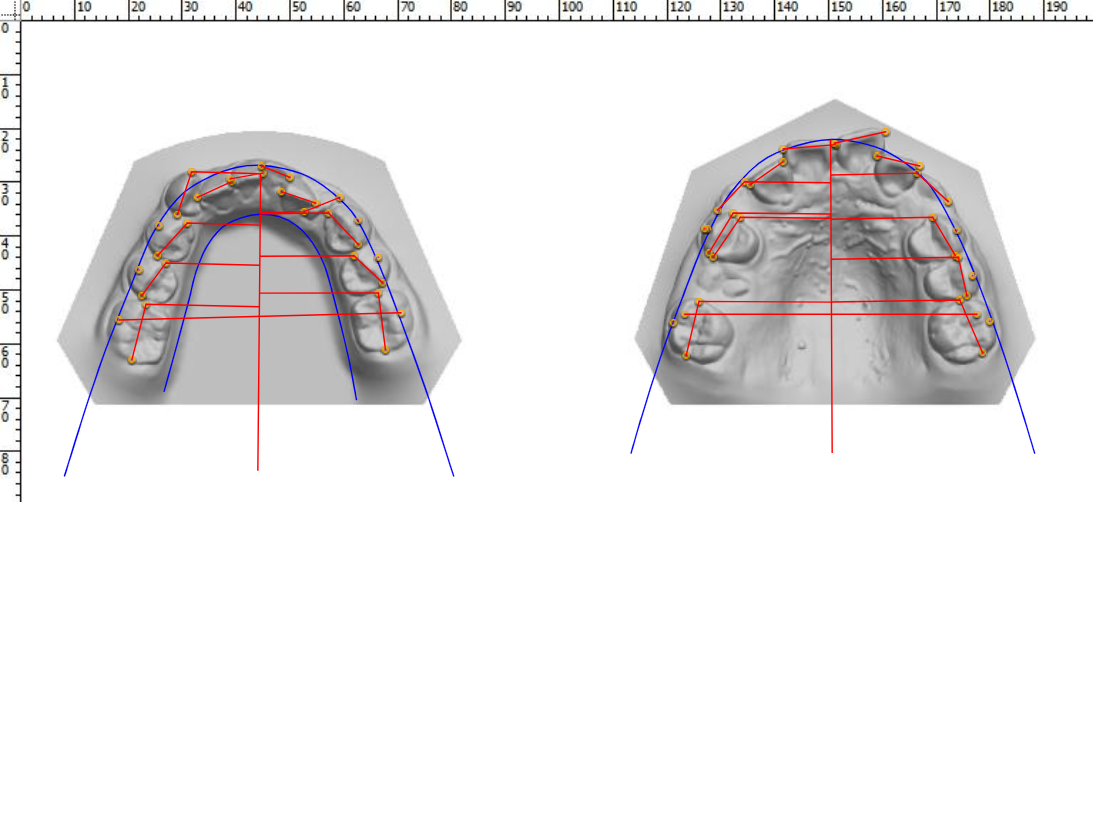

Many of us are not born with picture perfect teeth. For the straight teeth and alignment many people are searching for, braces is a common and effective treatment. Precision Dental Care uses the latest X-Ray technology to trace and model your teeth for your unique dental needs. From crooked teeth to alignment issues, braces can solve a variety of oral concerns.